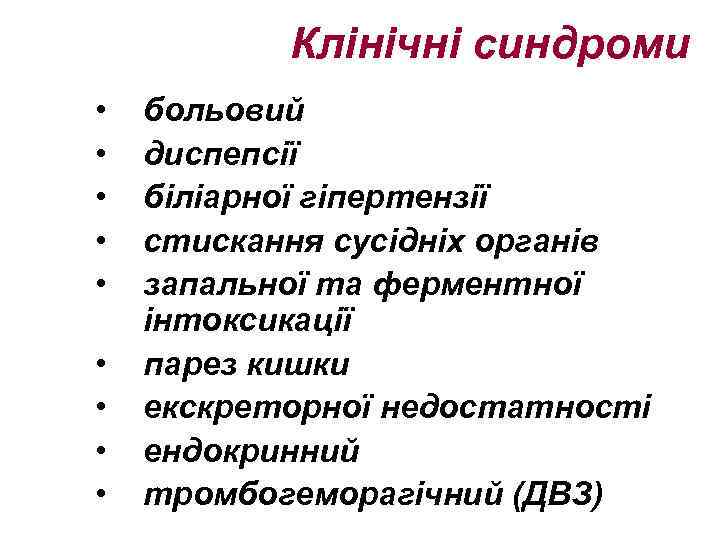

Клінічні синдроми • • • больовий диспепсії біліарної гіпертензії стискання сусідніх органів запальної та ферментної інтоксикації парез кишки екскреторної недостатності ендокринний тромбогеморагічний (ДВЗ)

Клінічні синдроми • • • больовий диспепсії біліарної гіпертензії стискання сусідніх органів запальної та ферментної інтоксикації парез кишки екскреторної недостатності ендокринний тромбогеморагічний (ДВЗ)